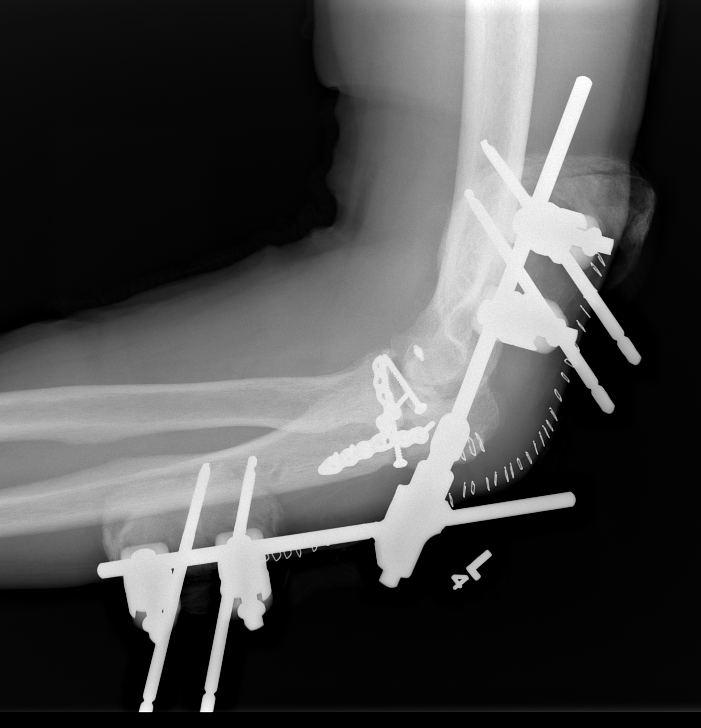

Hinged external fixation

Distal humeral axis

- confirm center of rotation on lateral

- protect ulna nerve

- place guide wire in center of rotation

AO surgery reference hinged external fixator

Lateral humeral pin | Medial humeral pin | Ulna pins |

---|---|---|

Anterior to radial nerve |

Posterior to ulna nerve |

Subcutaneous border of ulna

|